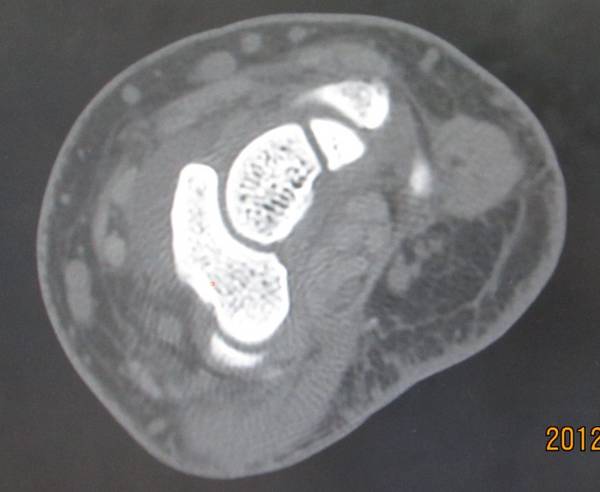

舟骨骨折

一侧皮质断裂

1.jpg

2.jpg

3.jpg

4.jpg

5.jpg

平片不明显,幸亏做了CT

6.jpg

8.jpg